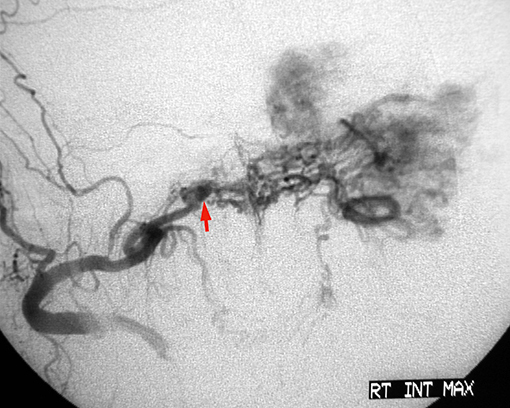

Aνάλογα με το μέγεθος και τις επεκτάσεις, αιματώνονται από διάφορετικές αρτηρίες. Στο αρχικό στάδιο που ο όγκος εντοπίζεται στον πρόσθιο ρινοφάρυγγα και την οπίσθια ρινική κοιλότητα, η αιμάτωση γίνεται από το τελικό τμήμα της έσω γναθιαίας αρτηρίας (με τον σφηνουπερώιο κλάδο να τροφοδοτεί το ρινικό τμήμα, και τον πτερυγοειδή κλάδο το ρινοφαρυγγικό τμήμα του).